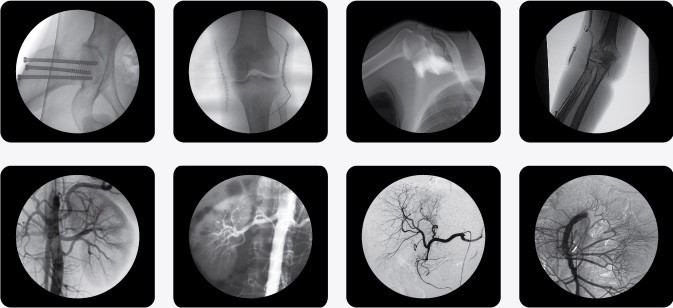

同類生產(chǎn)廠家還有南京卡普,肯定有不少人對(duì)南京卡普小C型臂價(jià)格報(bào)價(jià)多少錢一臺(tái)?感興趣,在這里隆重向大家介紹南京普愛PLX7000C型C型臂X光機(jī),其廣泛應(yīng)用于介入科、骨科、外科、矯形外科、泌尿外科、脊柱外科、腹部外科、疼痛科、心臟科、消化科、婦科及手術(shù)室等。 自主開發(fā)掌握了國(guó)內(nèi)領(lǐng)先的數(shù)字脈沖劑量智能控制技術(shù),在保證清晰影像的同時(shí),大幅降低射線對(duì)醫(yī)患輻射的危害,達(dá)到歐盟醫(yī)療器械相關(guān)要求。

以下是南京C型臂X光機(jī)PLX7000C的產(chǎn)品參考圖,點(diǎn)擊產(chǎn)品圖下方紅色的產(chǎn)品名稱可以直接進(jìn)入詳情頁面:

(普朗品牌產(chǎn)品--C型臂X光機(jī)PLX7000C